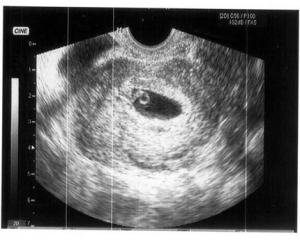

На 6 тижні вагітності по фото УЗД розмір плода встановить абсолютно чітко - це зовсім малесеньке, але вже цілком жива істота. Розмір плода фото УЗД показує дуже добре. Він досягає, всього на всього, 1,5 см. Саме на шостому тижні починають формуватися нервові закінчення в ручках і ніжках, а нервові клітини займають свої місця по всьому організму. Це говорить про те, що малюк скоро почне все відчувати, і буде поступово вчитися рухатися. За допомогою УЗД на цьому тижні вагітності лікар перевірить важливу особливість - як розвивається головний мозок плоду. До цього часу всі три частини «розумового відділу» дитини повинні бути сформовані. Фото УЗД допоможе виключити патології. Розмір плода фото УЗД для досвідченого лікаря може багато про що рассказать.Особенно це важливо, якщо є сумніви в правильному розвитку. З'являються невеликі пухирці, які незабаром стануть чудовими очима. Дивно, але зір - це той важливий орган, який буде формуватися протягом всієї вагітності і завершиться тільки після пологів. Починають формуватися легкі. В організмі все відбувається поступово, для кожного процесу є свій термін. Але завдяки таким знанням, ви можете, нарешті - то усвідомити, що всередині вас перебуває справжнє живе диво - ваш майбутній малюк. І нехай зараз - на шостому тижні, він зовсім не схожий на немовля, він вже є таким.

Розмір плода фото УЗД на даному терміні вагітності показує чітко і ясно. Але крім того УЗД в першому триместрі вкрай важливо для встановлення наявності патологій і загроз для життя як матері так і ребенка.Но все ж варто пам'ятати і про те, що не варто робити фото УЗД без показань лікар, а просто з цікавості побачити майбутню дитину. Справа в тому, що навіть якщо ви хочете побачити свою майбутню дитину цьому тижні вагітності, то вам це навряд чи вдасться.

Монітор покаже лише невелику точку на екрані, а вся отримана інформація від ультразвуку буде корисна виключно лікаря, а не жінці. Тому багато лікарів не радить проводити УЗД на занадто ранньому терміні, без вагомих на те причин.

Фото УЗД покаже, що на цьому тижні протікання вагітності розмір дитини досягає невеликої горошини. Але завдяки тому, що медицина сьогодні пішла далеко, УЗД може встановити розмір плода з точністю до міліметра. Як відбуваються виміри?

Для початку у малюка необхідно знайти куприк і визначити тім'яну зону. На фото УЗД це буде абсолютно невелику відстань, але все ж і його можна виміряти. Відстань між цими зонами називається довгою плода і на шостому тижні вагітності досягає всього пари міліметрів.

Фото УЗД розмір плода визначає точно і це важливо для першого триместру. Саме перше проведене УЗД допоможе лікарю встановити найбільш точний термін пологів. Це важливо в тому випадку, коли у вагітної до пологів не була регулярний або непостійний менструальний цикл або вона просто не пам'ятає необхідних дат. В основному, на шостому тижні УЗД проводиться для того, що б встановити достовірність вагітності - її наявність. До цього терміну матка починає збільшуватися і фото УЗД фіксує ці зміни. Для того, що б більш точно встановити розмір плода і термін вагітності за допомогою УЗД також проводять дослідження плодового мішка. Допоможе у встановленні термінів і серцебиття вашого малюка. Апарат УЗД вловлює скорочення сердечка, виводить їх на екран і динамік. Мама може насолоджуватися, а лікар завдяки цим звукам встановить термін розвитку ембріона, яким повинен бути розмір плода і визначить за допомогою УЗД безпосередньо сам термін вагітності і дату можливих пологів.